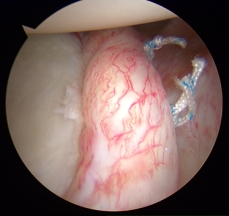

Schulterinstabilität

Die Schulter ist das Gelenk des Menschen mit der höchsten Beweglichkeit. Durch Stürze auf den abgespreizten Arm bzw. durch eine hohe Belastung der Schulter in der abgespreizten Position beim Sport kann es passieren, dass der Oberarmkopf teilweise oder vollständig luxiert („auskugelt“) und hierbei die sog. Gelenklippe von der vorderen Gelenkpfanne abgeschert wird. Speziell bei sehr jungen Patienten(unter 30 Jahren) verheilt diese nicht von selbst in der richtigen Position, sondern bedarf einer differenzierten Therapie. Mehrfaches „Herausspringen“ schädigt den Kapsel-Band-Apparat immer weiter und führt unweigerlich zur Funktionsverlust und Arthrose des Schultergelenkes. In unserer Sprechstunde wird im Rahmen der körperlichen Untersuchung die klinische Diagnose einer Schulterinstabilität gestellt. Die Untersuchung kann durch bildgebende Diagnostik (konventionelles Röntgen, MRT) ergänzt werden.

Bei einer Schulterinstabilität muss nicht immer operiert werden. Je nach Alter und sportlichem bzw. beruflichem Anspruch kann zunächst ein konservativer (nicht operativer) Therapieansatz gewählt werden. Wenn operiert werden muss, wird die Operation vollständig arthroskopisch durchgeführt. Hierbei wird meist die vordere Gelenklippe durch kleine bioabbaubare Knochenankerschrauben an der ursprünglichen Position auf der knöchernen Gelenkpfanne refixiert und es können auch Begleitverletzungen mitbehandelt werden.

Die refixierte Gelenklippe und Sehnen sind nur wenig durchblutet und heilen daher entsprechend langsam an der Gelenkpfanne wieder ein. Daher ist eine konsequente Nachbehandlung unumgänglich. In dieser Zeit werden Sie sehr engmaschig krankengymnastisch mitbehandelt, um einerseits die Einheilung zu gewährleisten und andererseits die Beweglichkeit zu erhalten. In der Regel beginnen unsere speziell ausgebildeten Physiotherapeuten ab dem ersten Tag nach der Operation damit, den für Sie durch den Operateur festgelegten Nachbehandlungsplan umzusetzen.